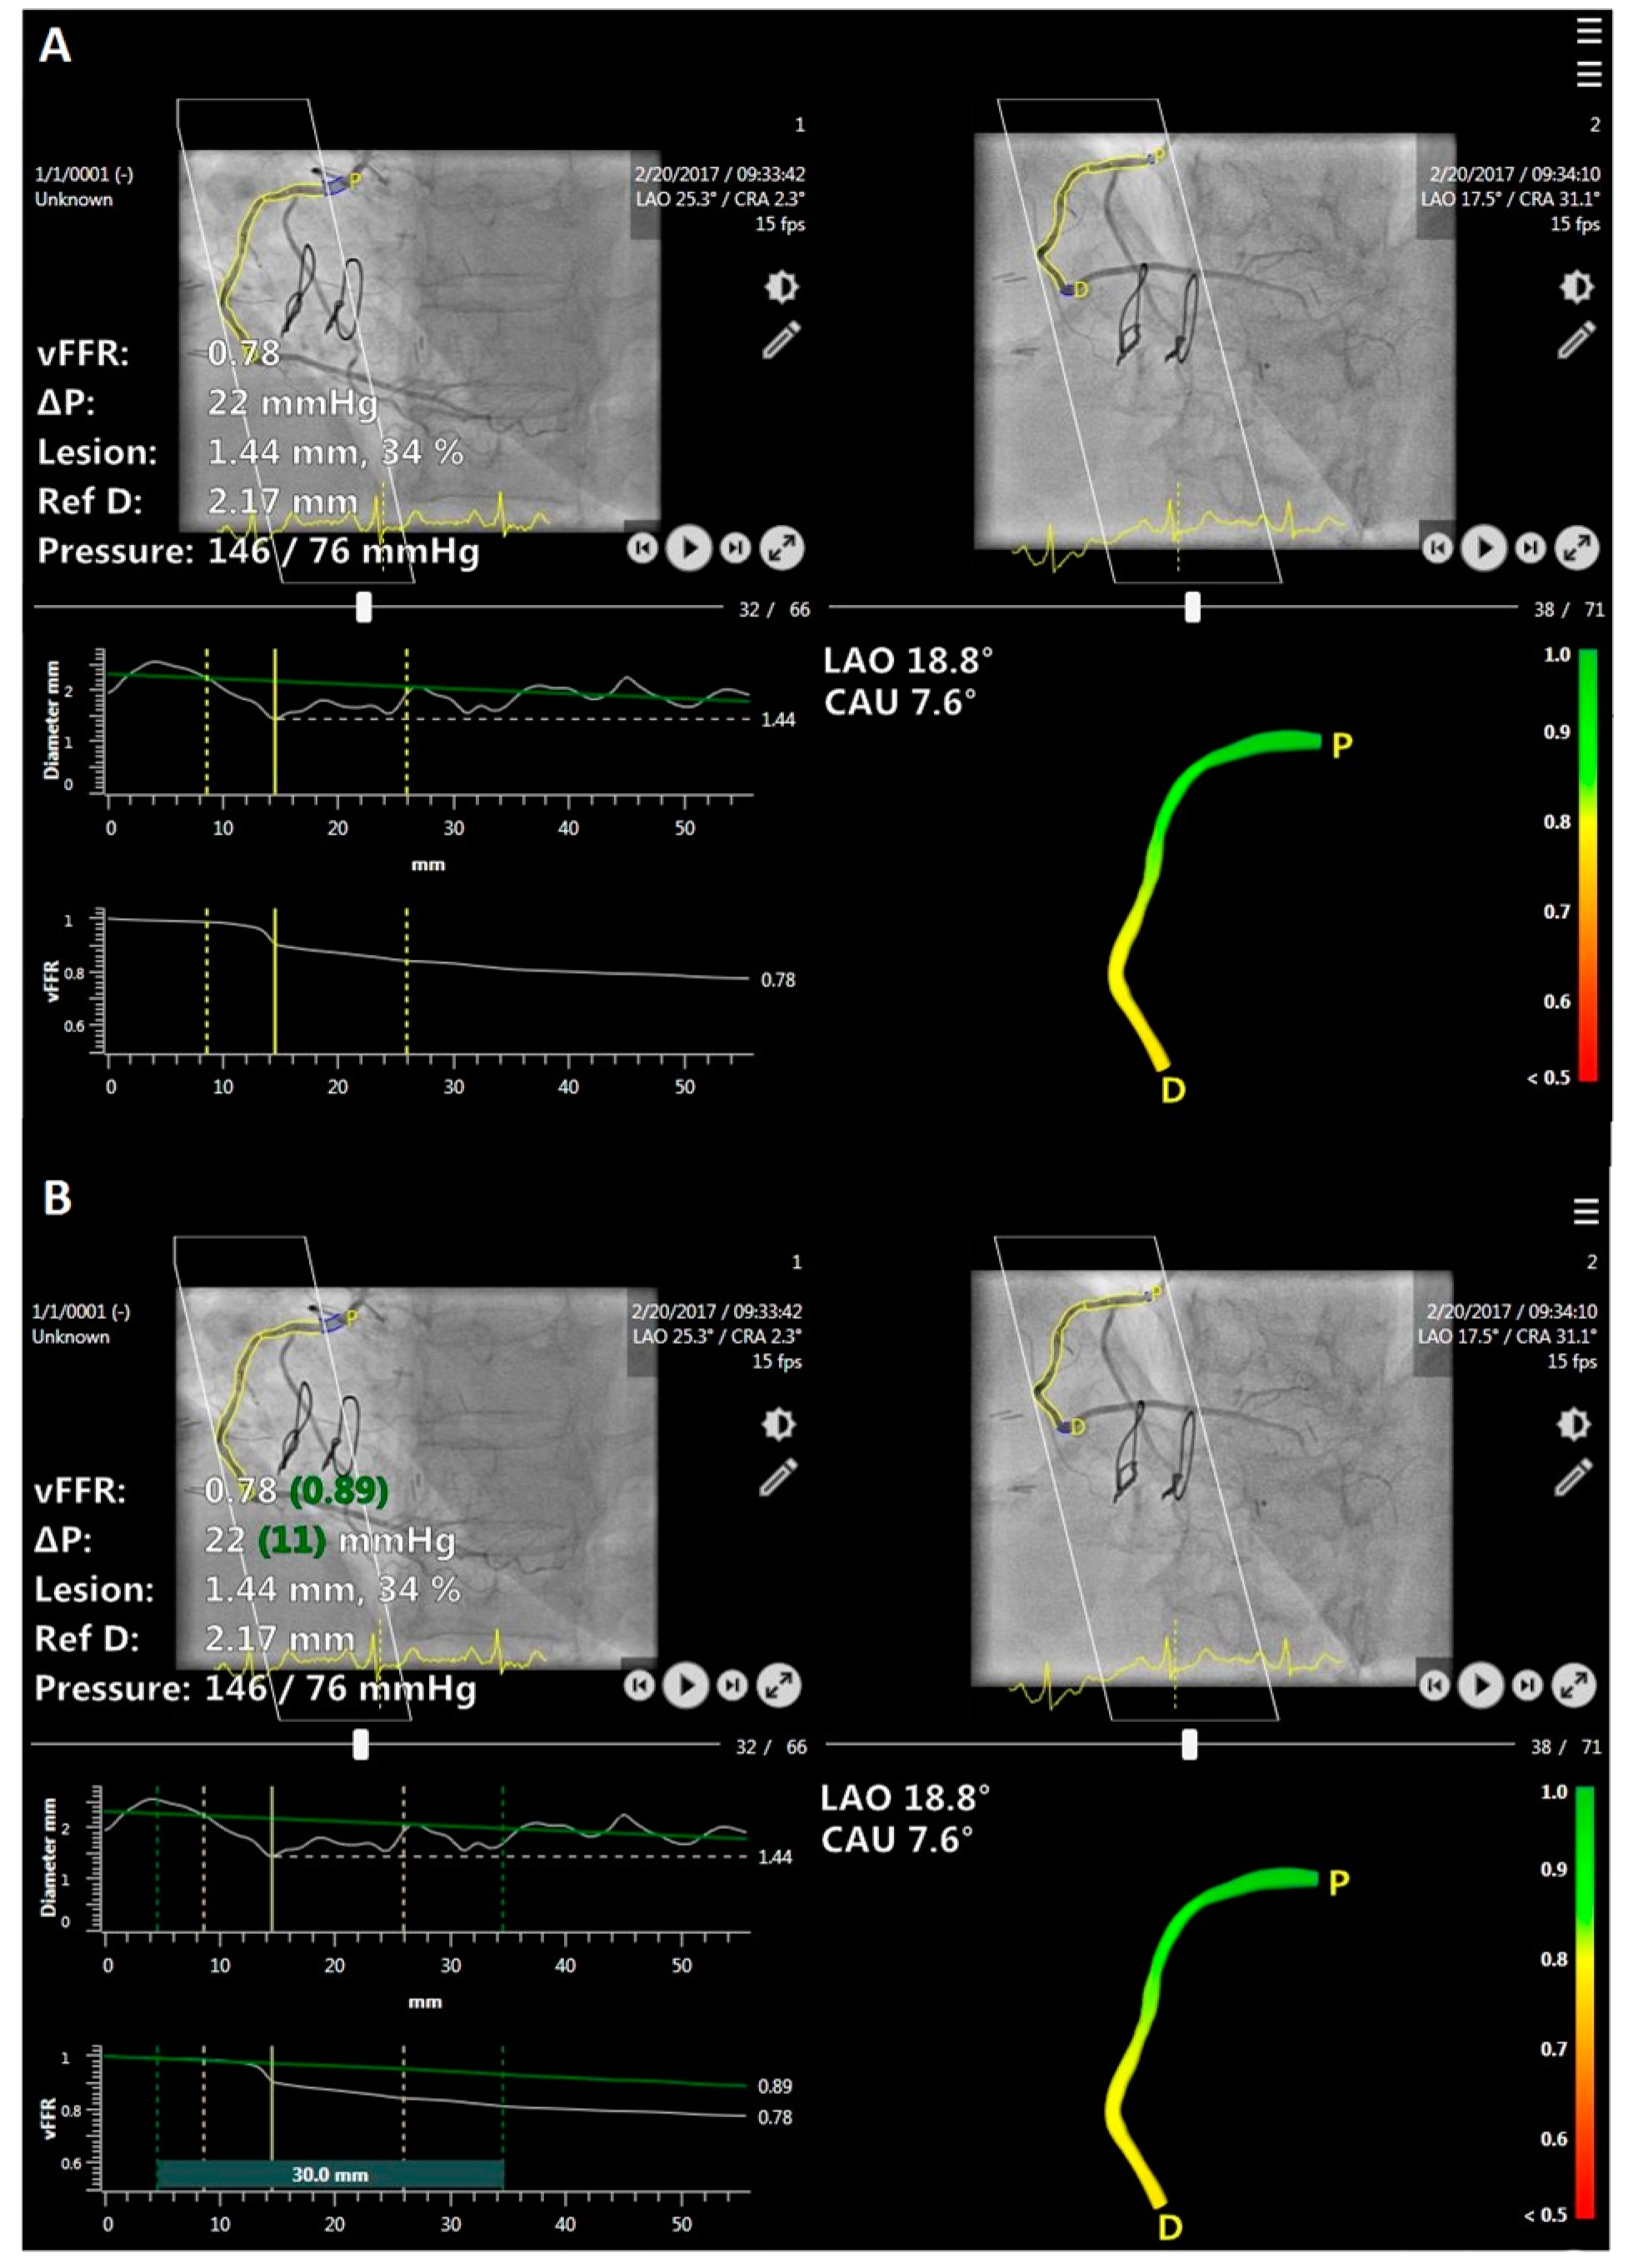

2.2. ‘Virtual Stenting’ (Residual) vFFR Analysis